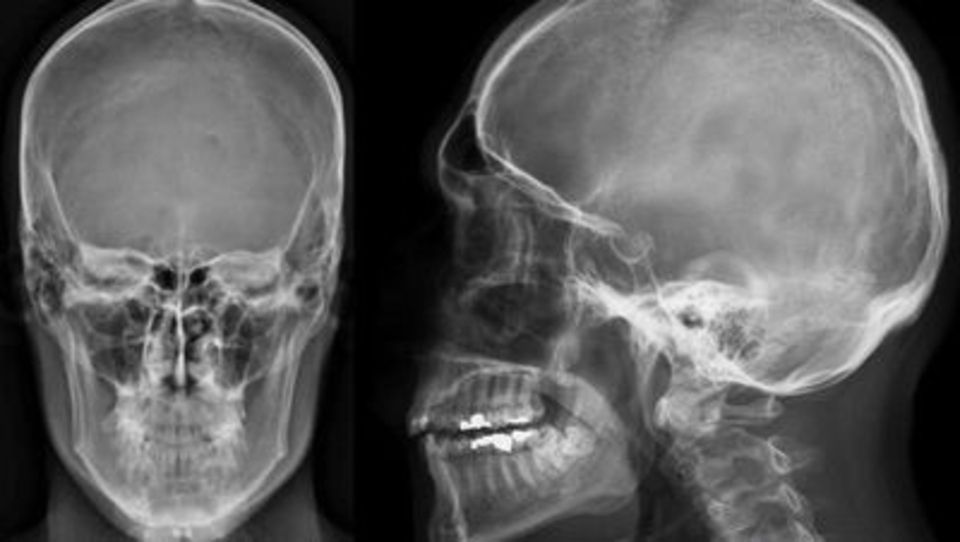

Eseguiamo radiografie dentarie, come ortopantomografia e teleradiografia del cranio, spesso necessarie per pianificare chirurgie orale e altri interventi. Siamo particolarmente apprezzati per la nostra capacità di fornire radiografie dello scheletro per la valutazione di patologie sistemiche, urografia, clisma opaco e RX toracico, dell’esofago, dello stomaco e del duodeno.